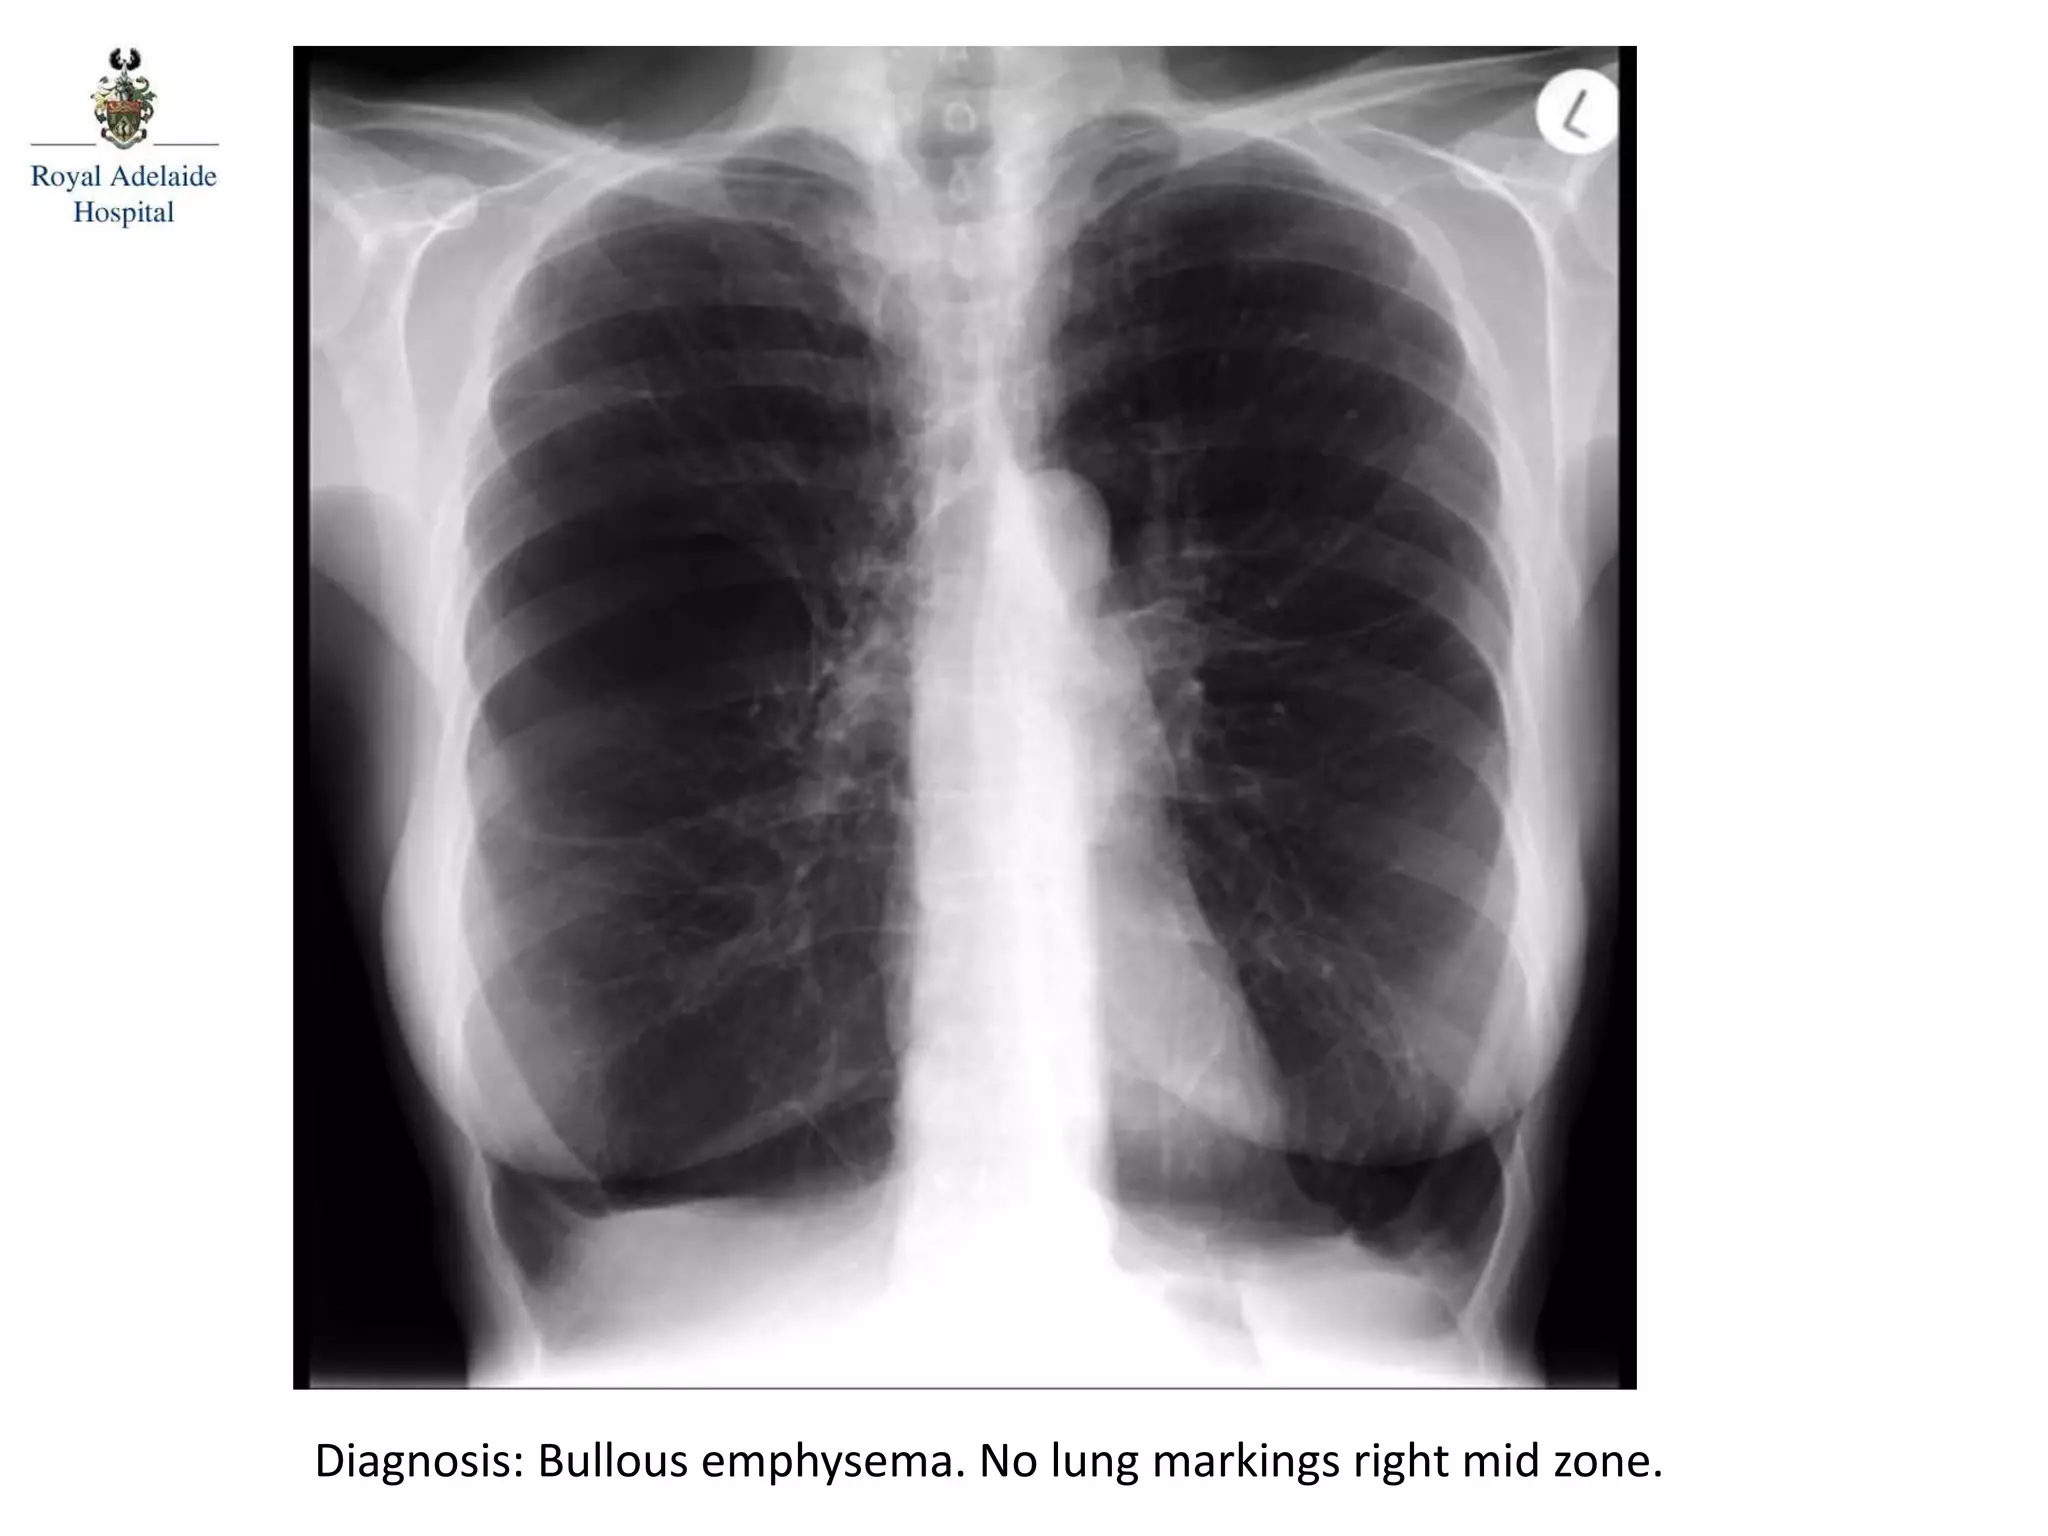

Diagnosis: Bullous emphysema. No lung markings right mid zone.